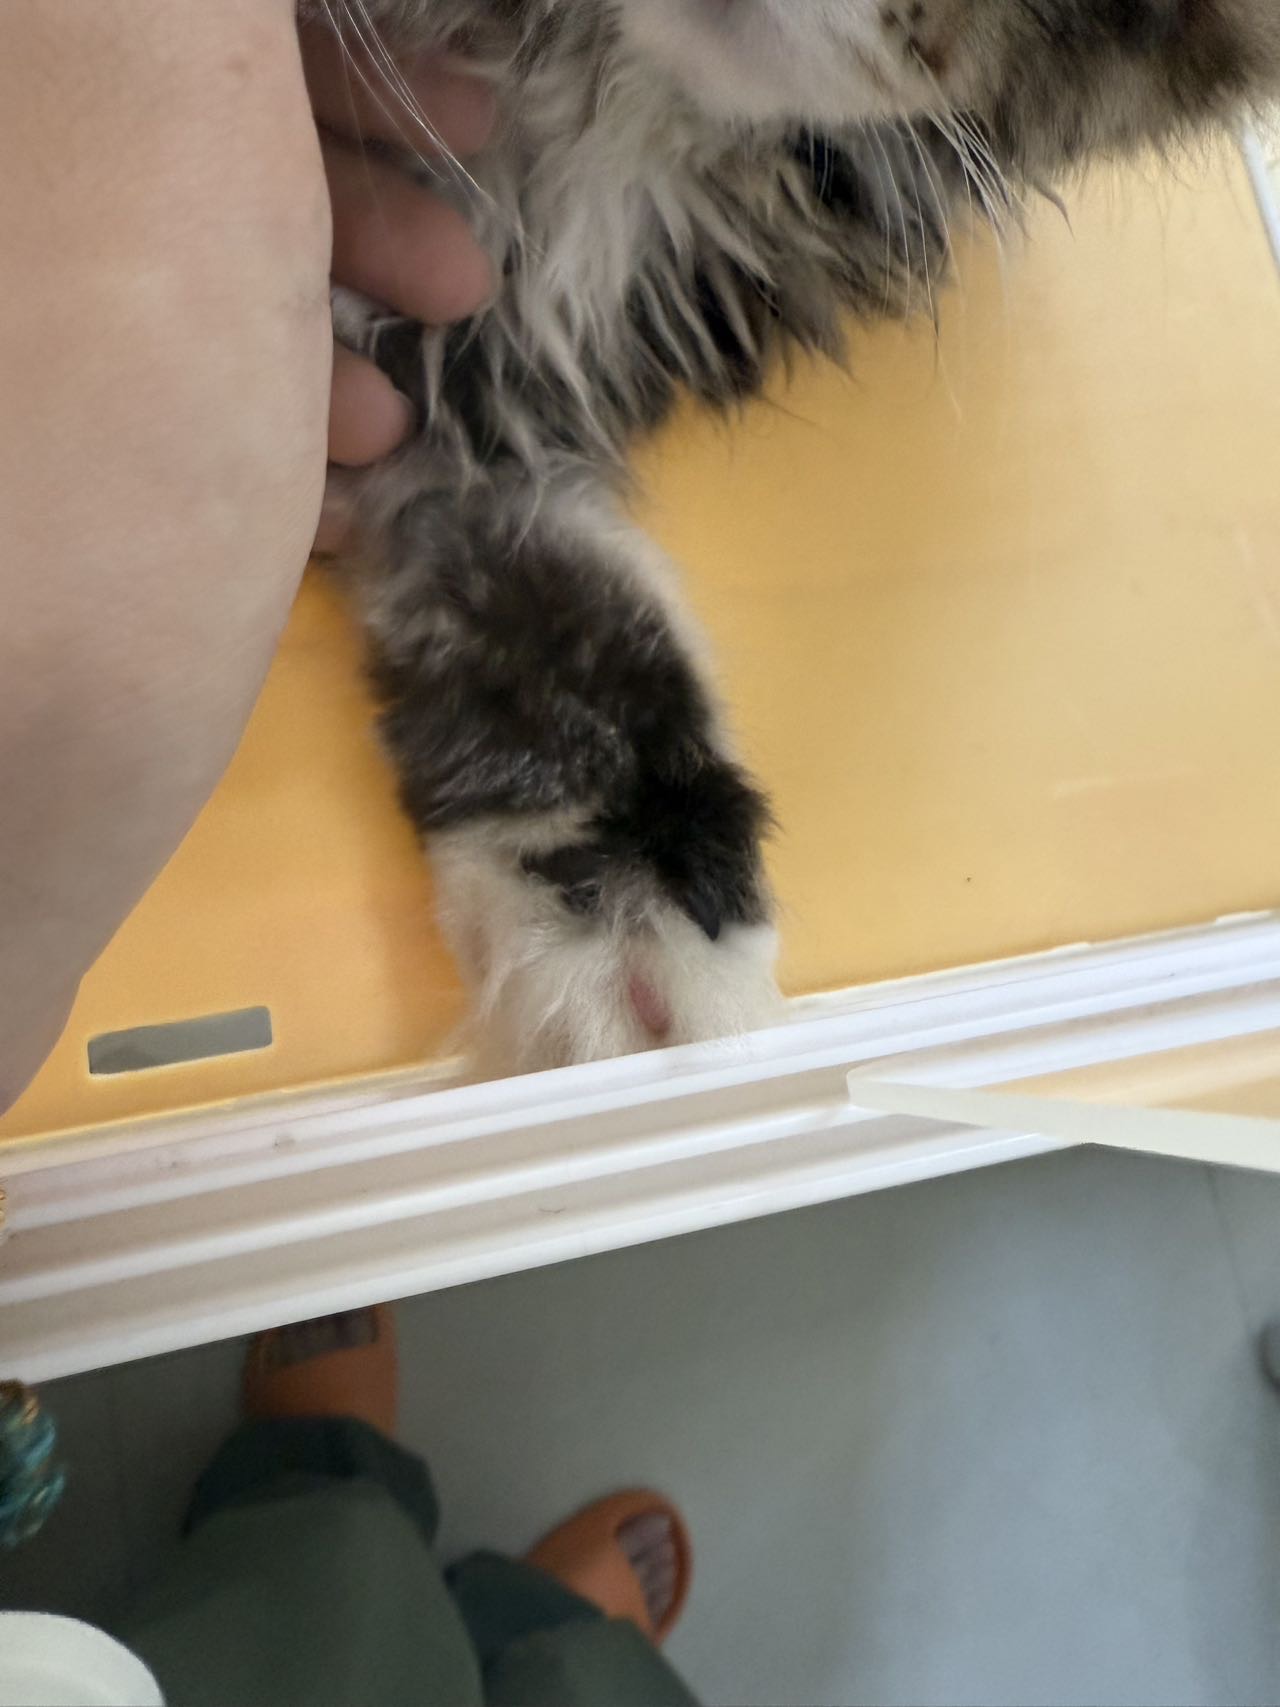

前天给他剪指甲的时候不小心把脚趾头上的皮给剪破了,用碘伏消过毒了。今天看了一下发现那只爪子的肉垫和那个脚趾头变黑了。但是其他活动都正常。需要去医院吗?萌宠医4365 | 图文问诊 | 2025.06.20 10:32:25